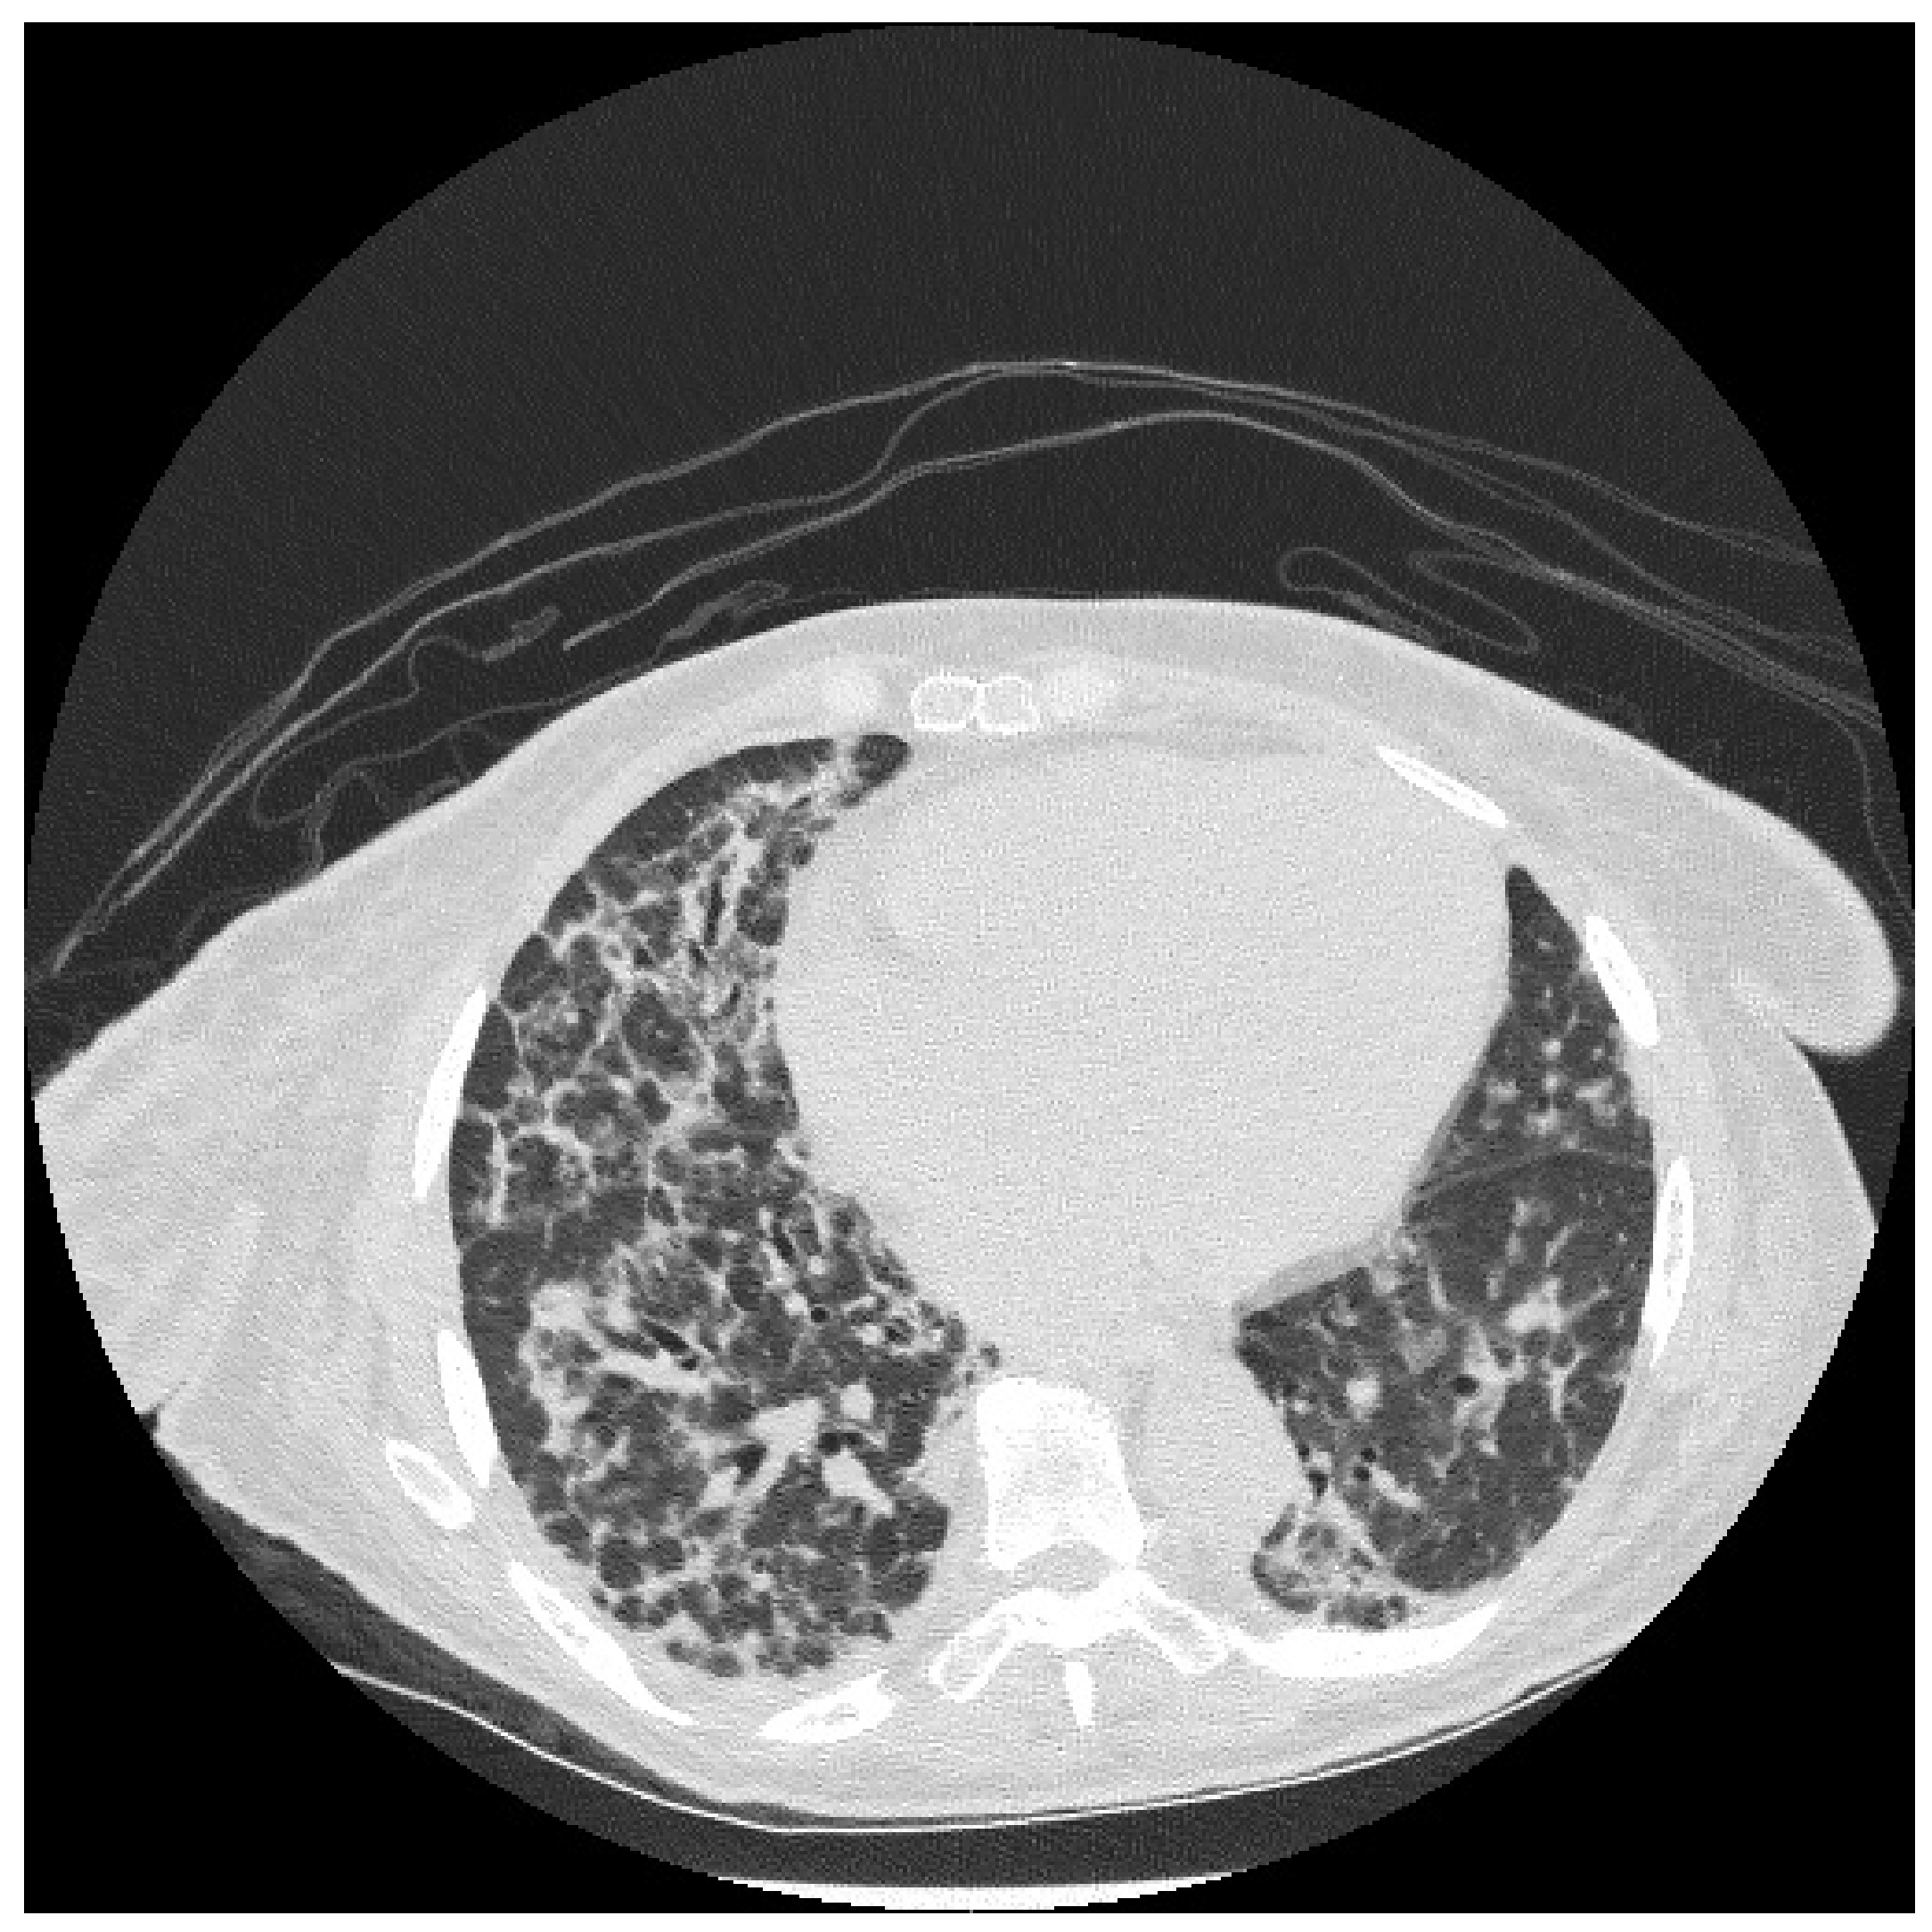

6.2. Histopathologic and Radiographic Findings in Myositis-Associated ILD